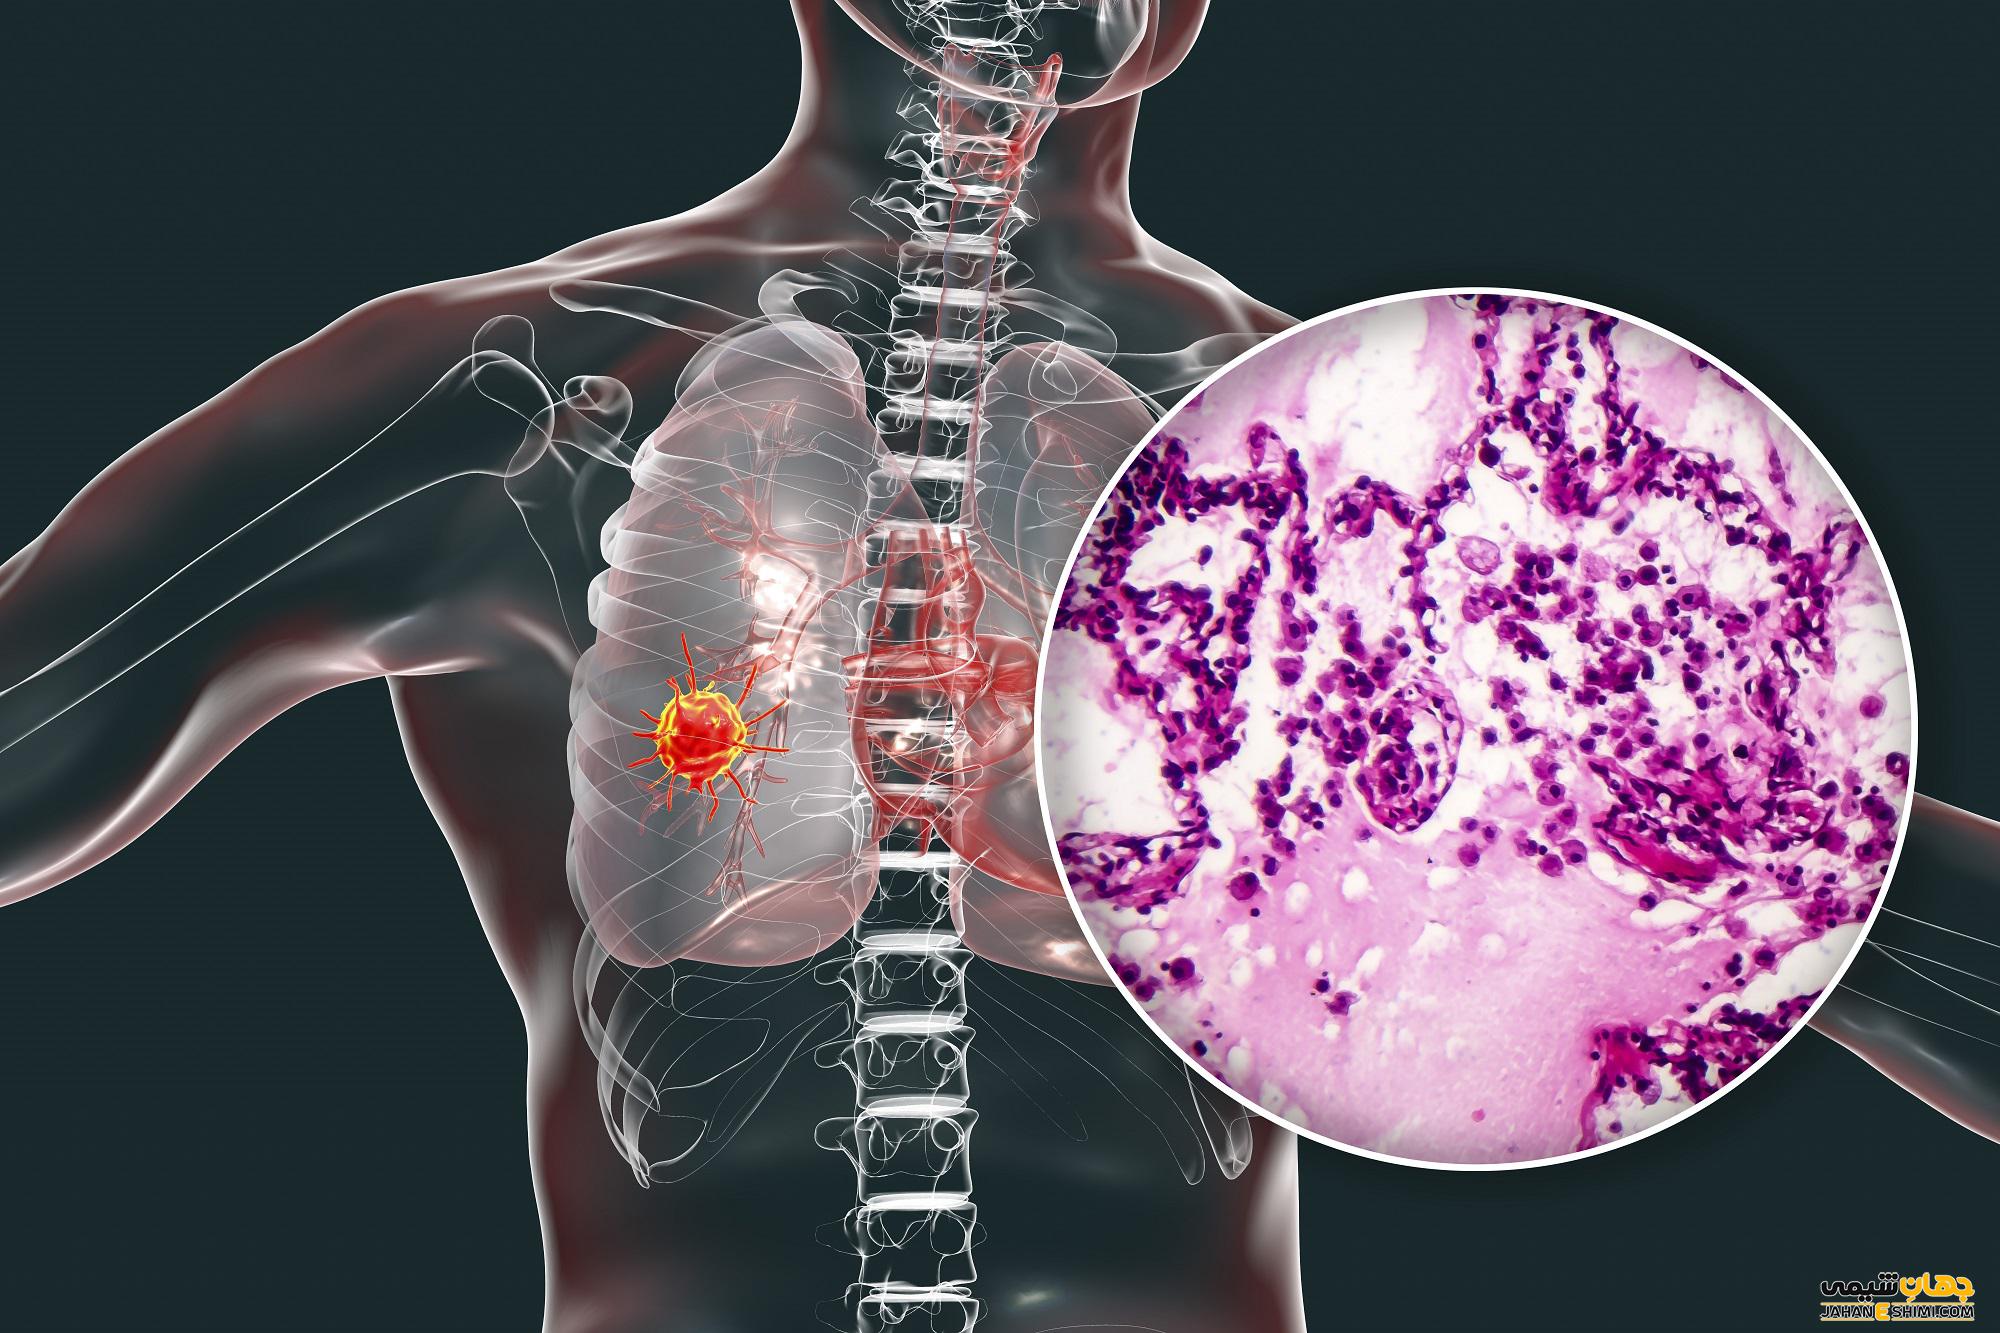

سرطان ریه

سرطان ریه علت اصلی مرگ ناشی از سرطان در ایالات متحده است. این عارضه معمولاً نتیجه سیگار کشیدن است ، اما در افرادی که مرتباً در معرض دود سیگار قرار گرفته اند یا حتی در افرادی که اصلاً سیگار نکشیده اند نیز ممکن است رخ دهد.

دود در صورت استنشاق با بافت ظریف ریه تماس مستقیم پیدا می کنند. دود سلول های ریه را از بین می برد و با قرار گرفتن در معرض طولانی مدت ، آسیب جبران ناپذیری ایجاد می کند.

دو نوع سرطان ریه وجود دارد: سرطان ریه سلول کوچک که عمدتا در افراد سیگاری رخ می دهد و سرطان ریه سلول غیر کوچک که اصطلاحی برای انواع مختلف سرطان های ریه است.